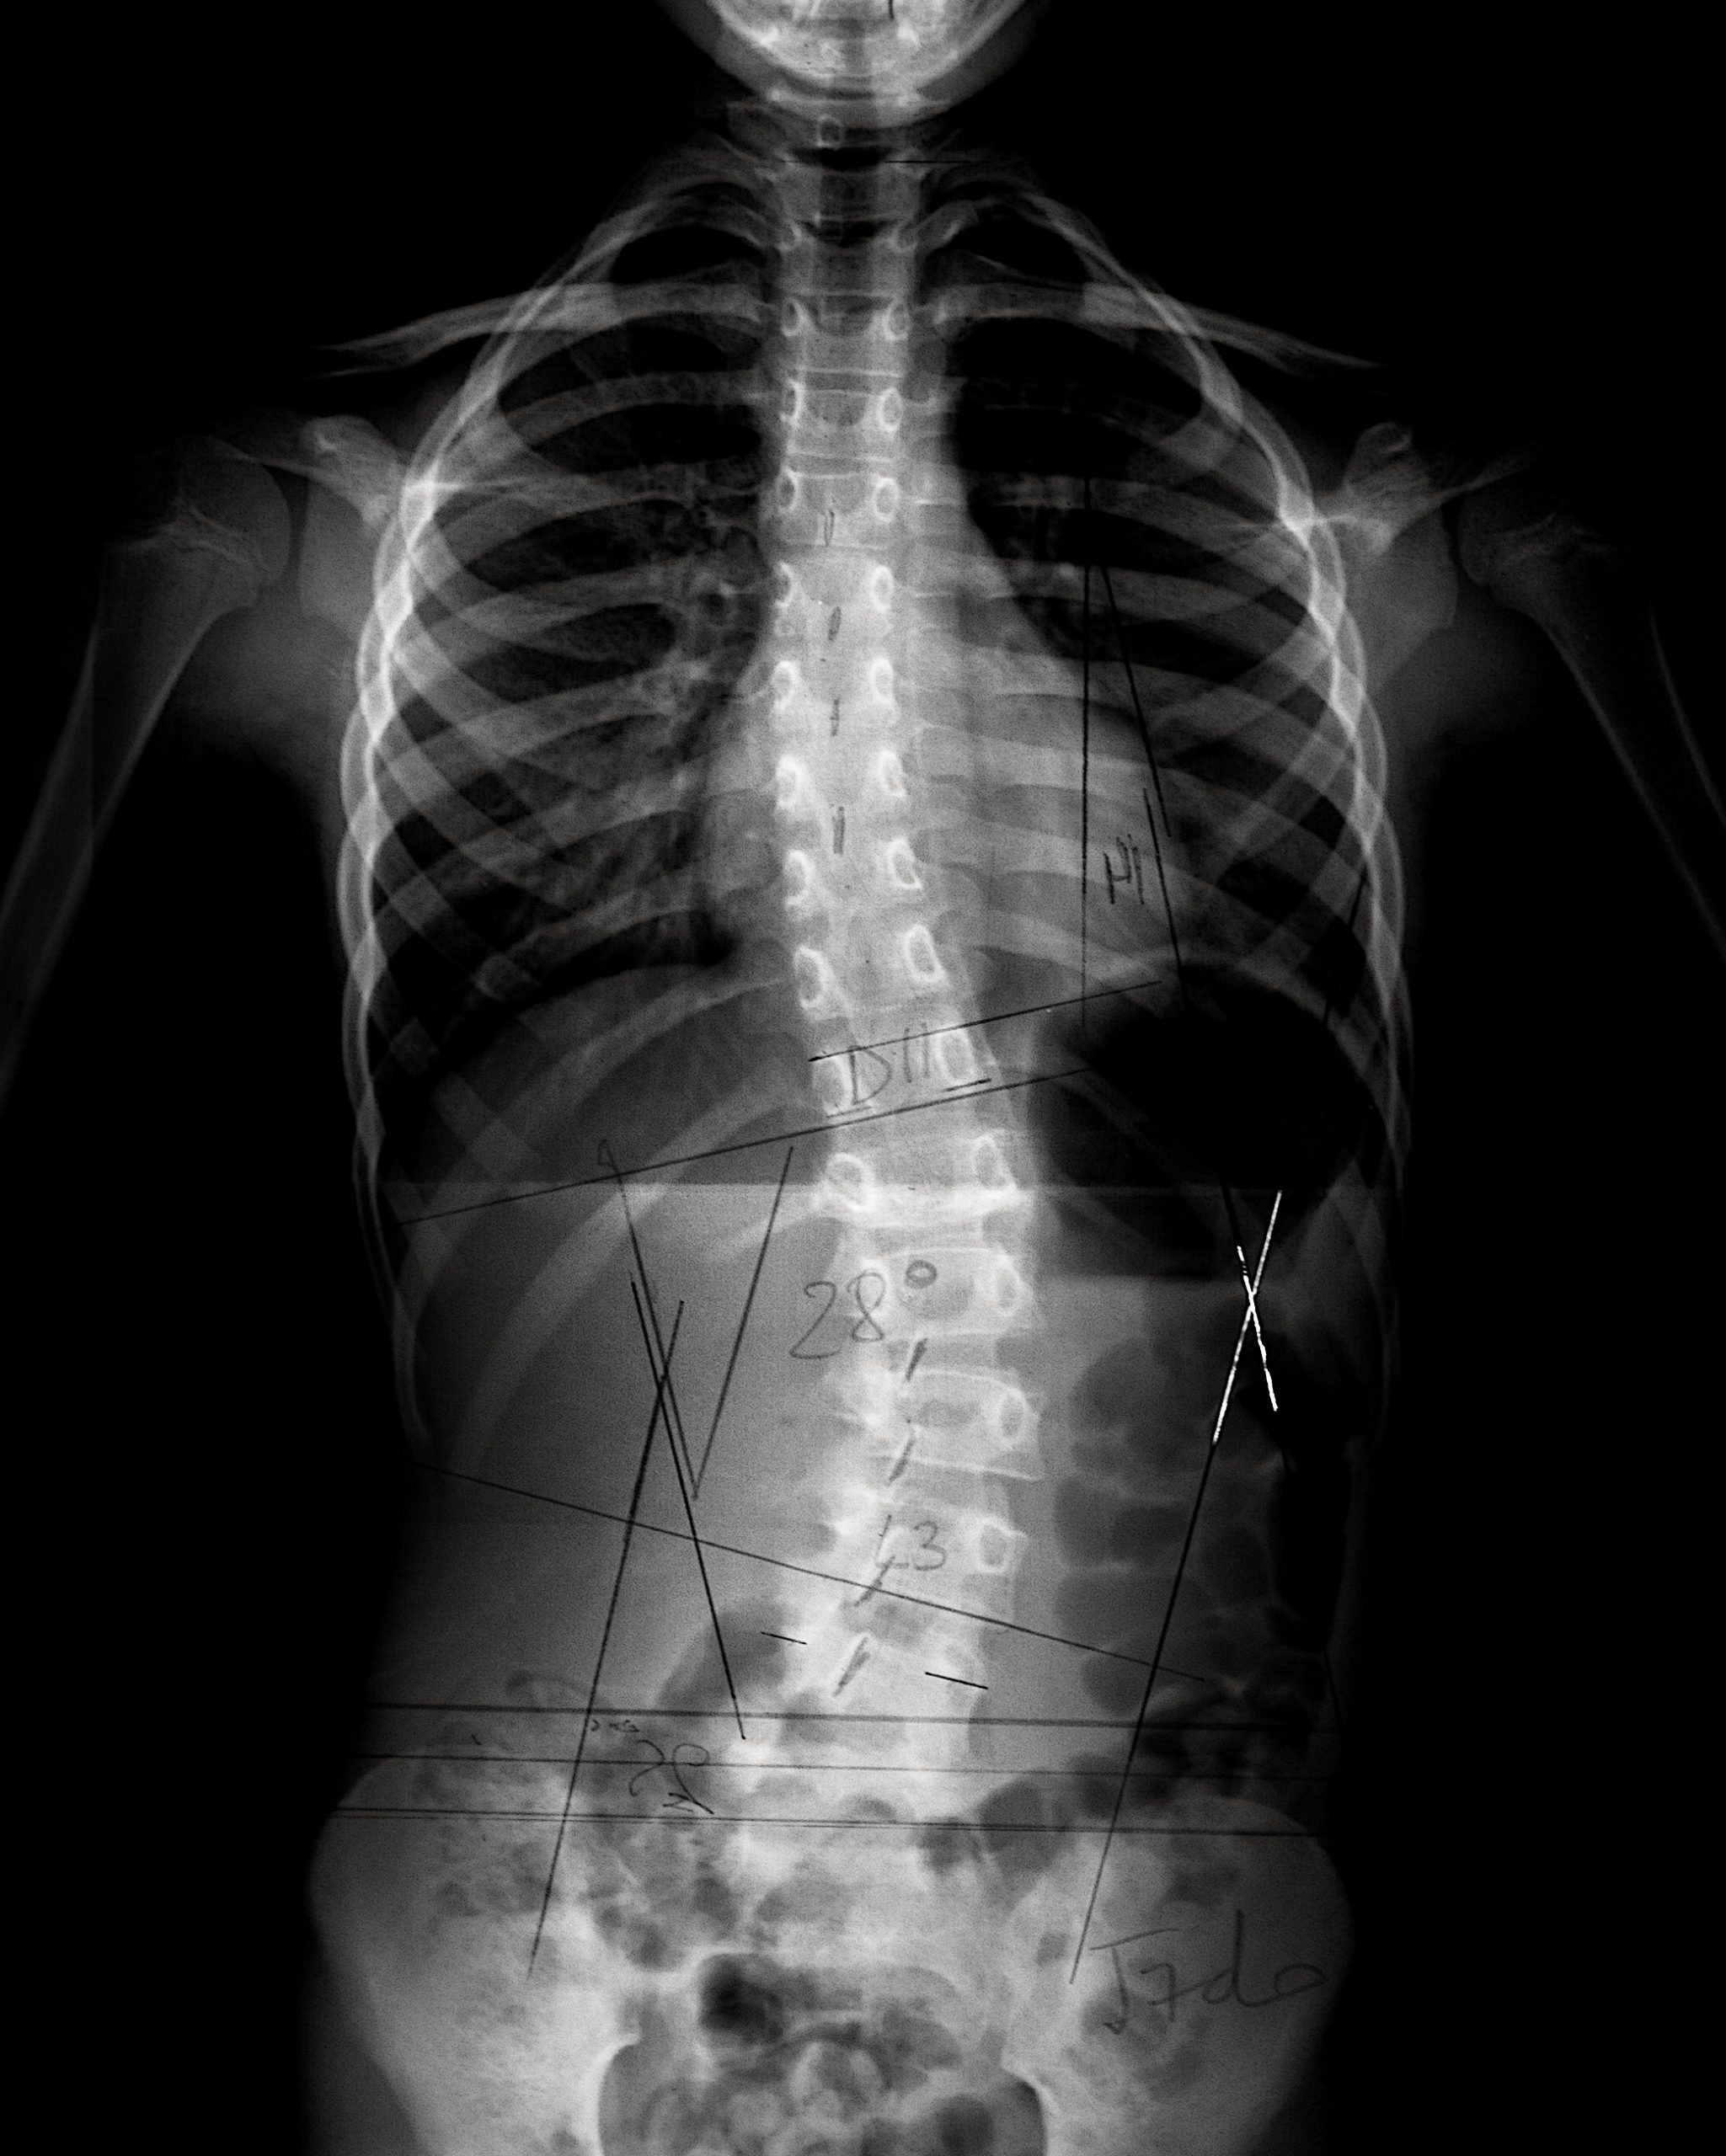

Columna es una reflexión profunda y emotiva sobre la escoliosis idiopática adolescente, que no solo aborda la enfermedad, si no también las complejas relaciones humanas y el proceso de sanación personal. Sonia Celma se define por su visión que fusiona arquitectura, música y fotografía.